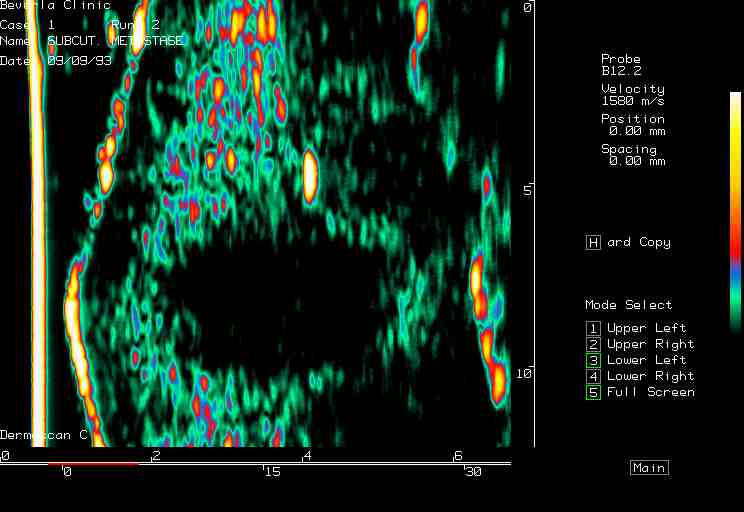

| Tumors |  Melanoma, forearm |

Metastasy, forearm |

Kaposi sarcoma |